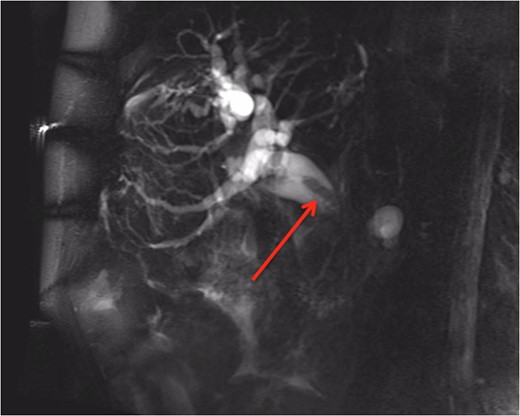

An 84-year-old man presented to the Emergency Department with a 3-week history of jaundice. He reported recent dark urine and weight loss of 8 kg over the preceding 3 months. The patient had a previous history of metastatic colorectal carcinoma, with a right hemicolectomy four years ago and a left hepatectomy one year ago for liver metastases. Bloods revealed a bilirubin of 224 U/L and raised liver enzymes consistent with an obstructive picture. He was admitted to the hospital and underwent a magnetic resonance cholangiopancreatography (MRCP). MRCP (Fig. 1) showed obstruction of the biliary tract transitioning at the ampulla. An endoscopic retrograde cholangiopancreatography (ERCP) demonstrated no choledocholithiasis; however, showed a likely malignant stricture. A sphincterotomy was performed, the common bile duct was dilated, and a biopsy and bile duct brushings were taken. As the patient was a poor surgical candidate, a metallic stent was inserted. Histology of the bile duct biopsy showed intestinal differentiation and was morphologically similar when compared to the patient’s previous resected colorectal liver metastases. Bile duct brushings showed malignant cells consistent with adenocarcinoma. Immunohistochemistry was cytokeratin-7(CK-7) negative and CK-20 positive, favouring an intrabiliary colorectal metastasis over a new primary bile duct carcinoma. Post-metallic stent insertion, the patient had a resolution of his elevated bilirubin and was referred to Medical Oncology for palliative chemotherapy.

MRCP showing an obstruction of the biliary tract (identified with red arrow) transitioning at the ampulla.